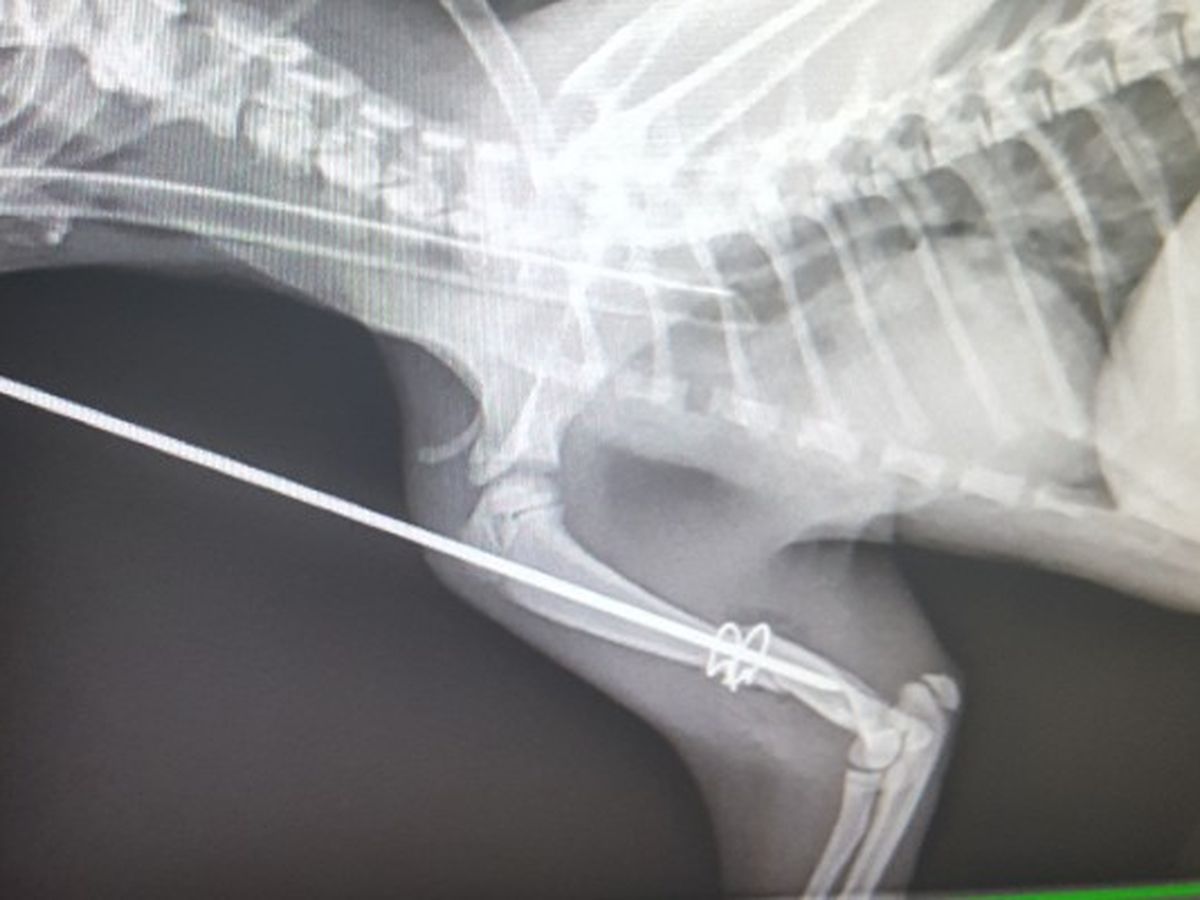

THIRD EDIT; The leg is broken really badly and she needs surgery right away. Please please please consider donating, at the money I have now I will have to amputate.